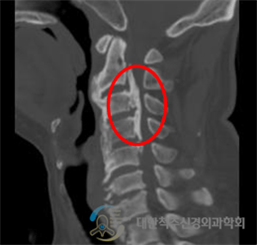

척추 뼈 사이의 움직임을 유지하면서 어긋나지 않도록 지지해 주기 위해 인대라는 것이 존재하는데, 목 부위 경추에서 꼬리뼈 근처의 천추까지 척추 전체를 위에서부터 아래까지 정렬을 유지하기 위해서도 인대가 존재합니다. 이러한 인대에는 여러 종류가 있는데, 척추의 정렬 및 안정화, 그리고 운동성을 유지하기 위해 존재하는 종인대 중 척추의 전방에서 지지하는 것이 전종인대이며, 척추체의 뒤쪽에서 지지하는 것이 후종 인대입니다. 이 후종 인대가 뼈처럼 단단하게 굳어지며 두꺼워지는 변화를 일으켜 척추관을 지나는 신경을 압박함으로써 신경장애 (척추신경근증 혹은 척수증)가 나타나는 질환을 후종 인대 골화증이라고 합니다.

이 질환의 원인은 불명확하지 않으나 주로 한국, 일본 등의 동양인에게서 상대적으로 자주 나타나고, 경추 후종 인대 골화증 환자의 부모나 형제에서의 발병률이 일반인보다 높은 것으로 보아 유전적, 인종적인 요소가 많이 작용하는 것으로 알려져 있습니다. 실제로 몇몇 유전자가 후종 인대 골화증에 연관되어 있다는 보고가 있습니다. 외상, 당뇨병, 비만, 면역 질환, 강직성 척추염, 미만성 골과다증 등과도 관련이 있다고 보고되고 있으며, 발생 부위는 주로 목 부분인 경추에서 발생하지만 흉추나 요추에서도 드물게 발생합니다.

많은 경추 후종 인대 골화증 환자는 무증상 또는 초기에 경부(목 부위) 통증과 위화감, 압박감의 증세만을 호소합니다. 그러다 진행이 되면 후종인대가 딱딱해지고 점차 커지면서 신경을 압박하여 팔이나 손의 저림, 통증, 감각 저하, 근력 저하로 시작하여 점차 다리의 근력 저하 및 감각 이상, 보행장애, 배뇨나 배변장애가 나타나며, 외상으로 인해 더 악화되거나 더 심한 경우에는 팔다리의 마비도 올 수 있습니다. 경추 후종 인대 골화증의 증상은 주로 신경근 압박에 의한 방사통 보다는 척수 압박에 의한 척수병증을 보이는 경우가 대부분입니다. 80-95%의 환자에서 증상은 천천히 진행되나 경미한 외상 또는 경추의 과도한 신전에 의해서 증상이 급격하게 악화되어 사지마비가 올 수도 있습니다.

단순 방사선 검사

후종인대 골화증의 경우 골변성을 동반하기 때문에 단순 방사선 검사상에서 발견이 가능한 경우도 있습니다. 하지만 정밀한 진단을 위해서는 전산화 단층촬영(CT), 자기공명촬영(MRI)가 반드시 필요합니다.

전산화 단층 촬영

후종인대 골화증 검사에서 가장 중요한 검사입니다. 전산화 단층촬영은 골화된 종괴의 모양과 크기, 척추관 협착과 척수 압박 정도를 정확히 알 수 있습니다.